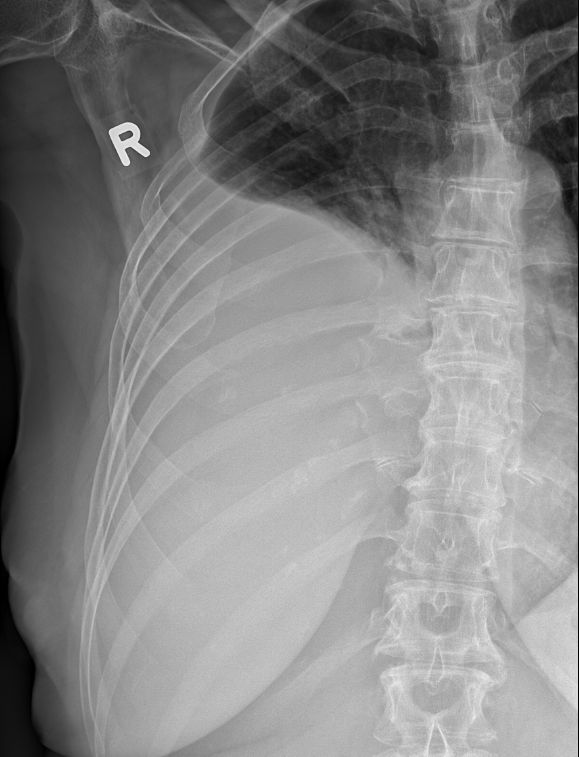

Hals-CUP 49jährige Frau mit Metastasen eines schleimbildenden Adenokarzinoms.